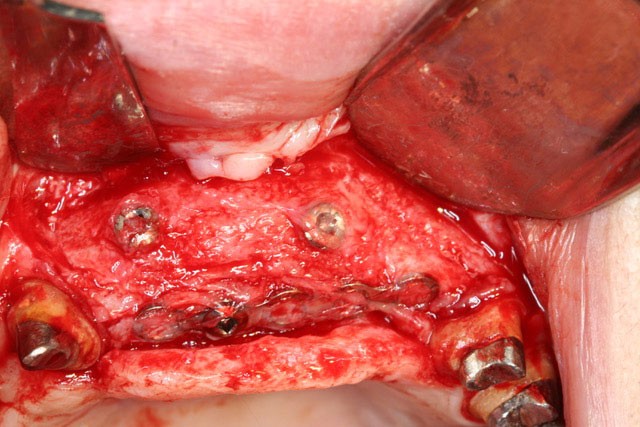

Dans la seconde partie de la soirée, le Docteur Surmenian, qui a intégré ces principes biologiques à ses protocoles d’augmentation osseuse, a pu développer ses nouvelles propositions thérapeutiques et leur apport comparativement aux procédures conventionnelles. Sa présentation, dont le titre interroge nos habitudes énonce l’ambition du concept chirurgical : « Faut-il tout changer pour simplifier et fiabiliser les augmentations osseuses ? » En convenant que les augmentations tridimensionnelles de la région postérieure mandibulaire constituent un défi thérapeutique que les techniques de greffes osseuses autologues en coffrage permettent de relever, le conférencier a rappelé à l’assistance toutes les difficultés associées à cette procédure. L’approche moins invasive suivie repose sur le choix de techniques de régénérations osseuses au moyen de particules cortico-spongieuses allogéniques et en respectant les fondamentaux biologiques tissulaires développés en première partie de soirée. Le recours à une plaque d’ostéosynthèse (Fast system®) maintenue à distance du site grâce à un ingénieux filetage résidant à la tête des vis de fixation offre une structure aisée à installer sur la crête à augmenter. Le dispositif rigide facilement stabilisé préserve le matériau venant combler l’espace du défaut, des pressions et tensions sus-jacentes. Le comblement est assuré à l’aide de particules cortico-spongieuses d’os allogène amalgamées à du PRF qui leur confèrent une consistance compacte (sticky bone).

La troisième approche consiste à libérer les lambeaux afin d’obtenir la laxité nécessaire à une fermeture sécurisée du site augmenté. Le relâchement du lambeau lingual décollé jusqu’à la ligne oblique interne est obtenu par un « brossage » apico-coronal de sa face interne à l’aide d’instruments spécifiques. Celui du lambeau vestibulaire repose sur le même principe (soft brushing). Les sutures finalisent la procédure en répartissant les tensions de repositionnement des lambeaux à distance (apical matress) et à proximité des berges de l’incision crestale. Le port des prothèses adjointes est prohibé et les sutures sont déposées 4 à 5 semaines après la chirurgie. Lors de la mise en place des implants (environ 4 mois après l’augmentation osseuse), le Docteur Surménian applique le principe de limitation de la compression des tissus durs en surdimensionnant son ostéotomie (surtout au niveau cortical). Ce principe l’a amené à sélectionner un implant (Anyridge® de Megagen) présentant une stabilité primaire majorée sans pour autant rechercher une élévation du couple d’insertion (signe de compression tissulaire).